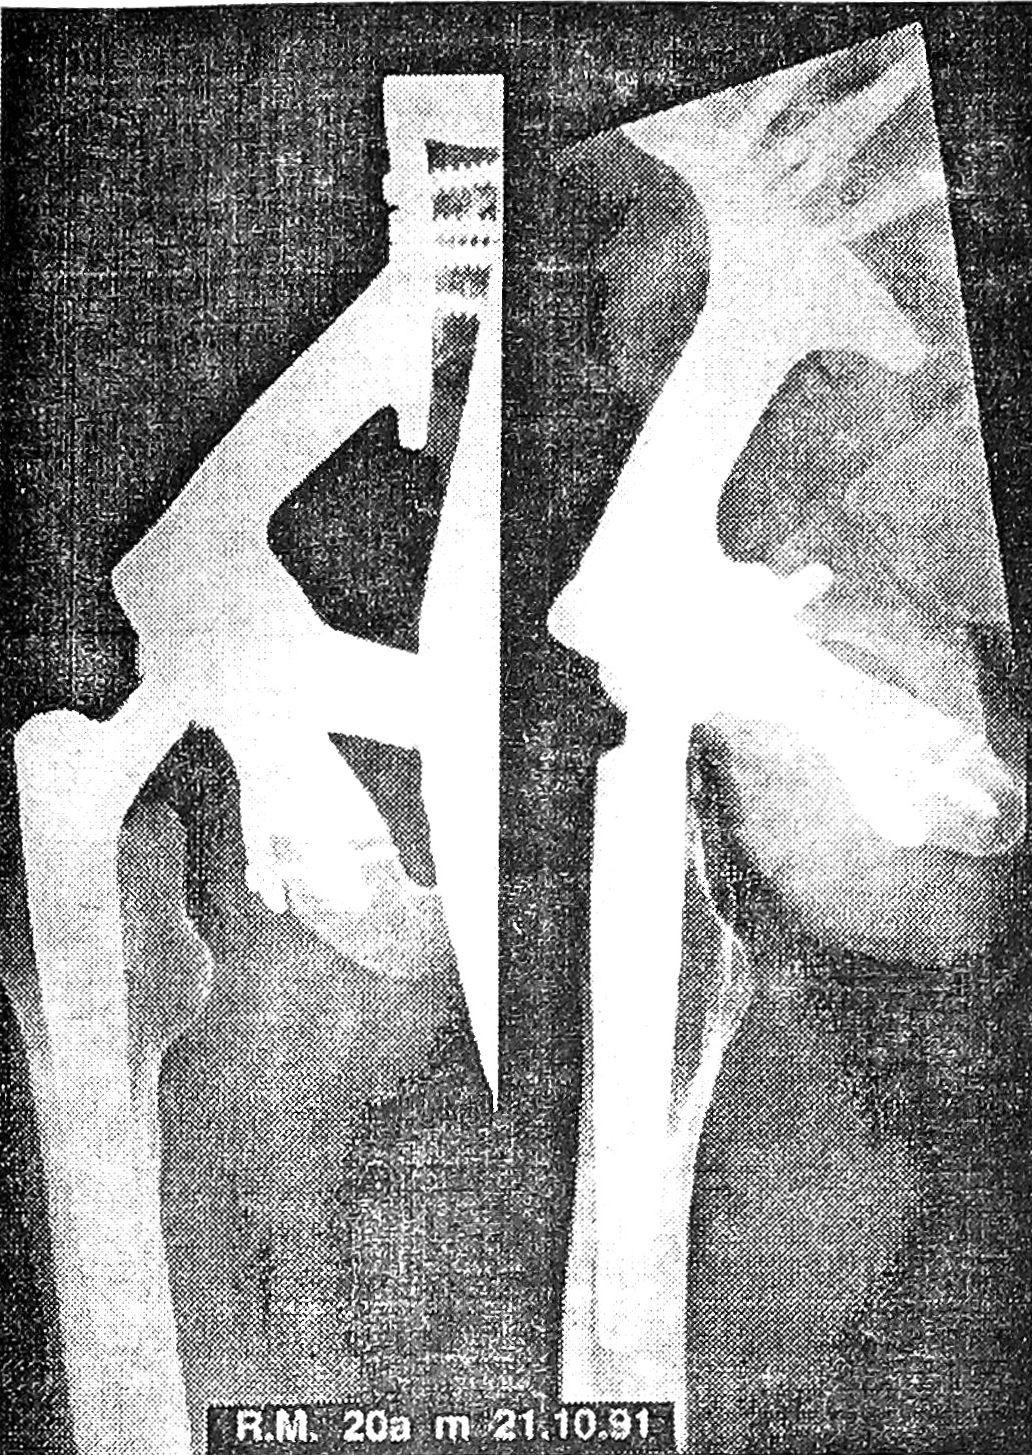

Рис. 1. Рентгенограмма больного 21 года с остеосаркомой дистального метафиза бедренной кости через полгода после обширной резекции и артродеза по Путти с применением интрамедуллярной фиксации гвоздем. Дефект медиальной части бедренной и латеральной части большеберцовой кости замещен аллотрансплантатом.